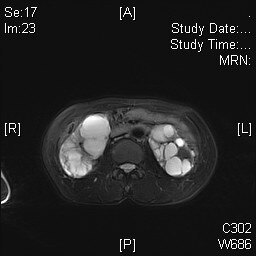

上周共行五臺(tái)多囊腎去頂減壓術(shù),有三例為做完一側(cè)多囊腎手術(shù),本次來(lái)做另一側(cè)多囊腎手術(shù)。 病例1,宋某某,患者女,2020.9.9在我院行右側(cè)多囊腎去頂減壓術(shù),現(xiàn)手術(shù)后一年,再次入院行左側(cè)手術(shù)。 右側(cè)腎臟術(shù)前磁共振圖像 右側(cè)腎臟術(shù)后磁共振圖像 2021.11.10行左側(cè)多囊腎去頂減壓術(shù),術(shù)后4天(11.15)拔引流管,順利出院。 病例2,畢某某,患者女,57歲,2019.5.8在我院行左側(cè)多囊腎去頂減壓術(shù),現(xiàn)手術(shù)后二年,再次入院行右側(cè)手術(shù)。 左側(cè)腎臟術(shù)前磁共振圖像 左側(cè)腎臟術(shù)后磁共振圖像 2021.11.13行右側(cè)多囊腎去頂減壓術(shù),術(shù)后5天(11.19)拔引流管,順利出院。 病例3,宗某某,患者女,58歲,2020.9.7在我院行右側(cè)多囊腎去頂減壓術(shù),現(xiàn)手術(shù)后一年,再次入院行左側(cè)手術(shù)。 右側(cè)腎臟術(shù)前磁共振圖像 右側(cè)腎臟術(shù)后磁共振圖像 2021.11.13行左側(cè)多囊腎去頂減壓術(shù),術(shù)后5天(11.19)拔引流管,順利出院。